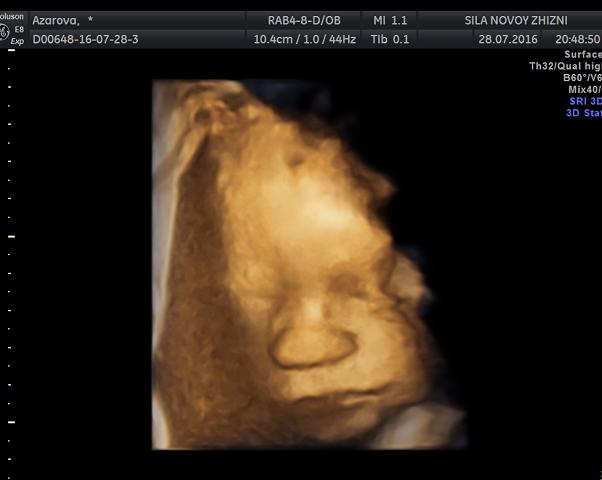

2 дня назад отметилась наша #31 неделька фруктом помелой🍊 На УЗИ ходили с мужем, смотрели на его маленькую копию😍

💥 УЗИ в "сила новой жизни"

💥 31 нед и 1 день 28.07.16

💥 весим 1759гр

💥 лежим правильно , головкой вниз👶

💥 делали допплер💓

💥 с плацентой, водами, пуповиной все гуд (боялась этого больше всего)👌

💥 полностью здоровы , счастливы и улыбаемся родителям😇